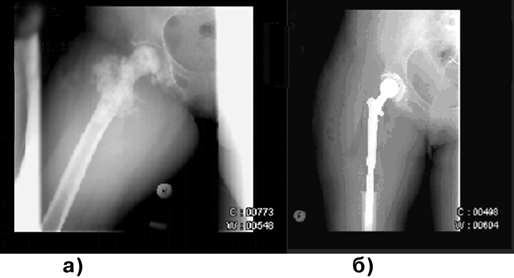

После курсов полихимиотерапии следует радикальное хирургическое лечение. При локализации опухоли в длинных трубчатых костях и небольших ее размерах могут производиться органосохраняющие операции в объеме резекции суставного конца или тотальное удаление длинной трубчатой кости с эндопротезированием (рис. 2). При опухолях с большим внекостным компонентом показана ампутация (экзартикуляция) на уровне вышерасположенного сегмента конечности. Для уточнения степени распространенности опухолевого процесса используются КТ и МРТ, а также планарная сцинтиграфия.

Рисунок 2. Остеосаркома бедренной кости:

а — до операции; б — после операции